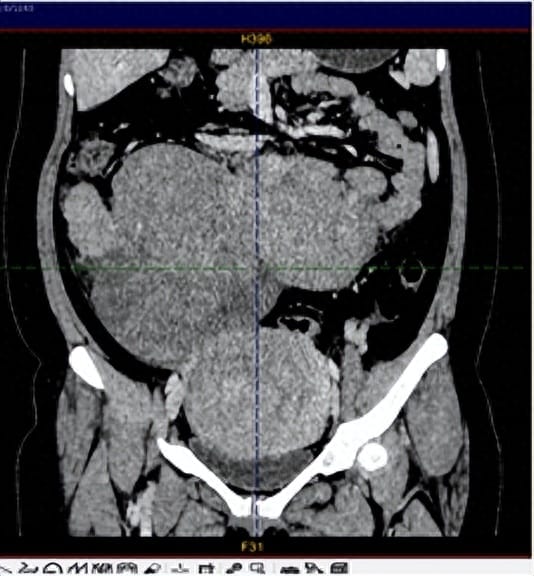

术后切下的巨大肿物

针对患者病情,科室组织了胃肠外科、麻醉科、影像科、病理科、重症医学科多学科会诊,并对术中可能出现的情况做了充分的评估及准备。手术当天,打开腹腔,大家都倒吸了一口凉气,肿块与大网膜及肠管致密粘连,肿物表面布满了怒张血管,仔细探查,发现肿块已经充满整个腹腔。在麻醉科和手术室医护人员的密切配合下,妇科周建斌主任团队联合胃肠外科单汉国主任,沉着冷静,小心仔细地将肿物分离出来并切除,手术非常顺利,术中血压、心率平稳,出血很少。在妇科医护人员的精心治疗与悉心护理下,患者恢复很好。非常庆幸的是,肿块病理报告是良性的播散性平滑肌瘤。出院时,患者紧紧握着周建斌主任的手,“南华附二妇科帮我解决了这么大的难题,确实是了不起!”